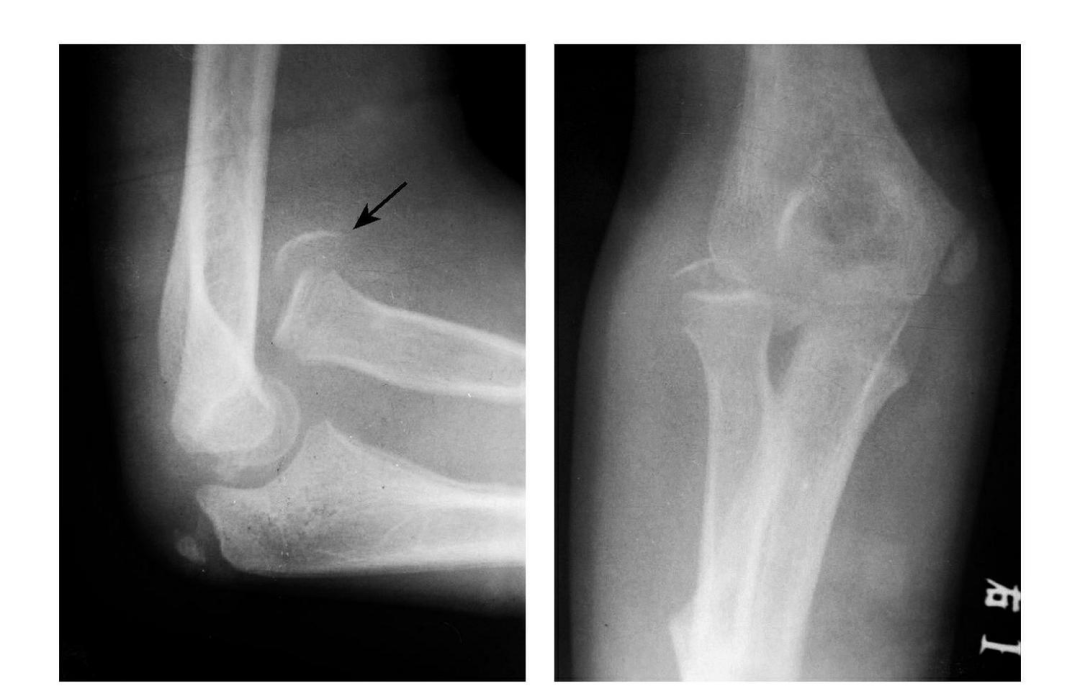

(7)Hahn-steinthal 骨折

全肱骨小头骨折,为一种少见的关节内骨折,多见于成年人。常由于跌倒时手过度伸直或在屈肘时因桡骨小头撞击肱骨小头,并同时有外翻力存在时发病,亦可伴有滑车骨折与内侧副韧带的撕裂。

例 1:肱骨小头基底部呈冠状面骨折,骨折块呈半球状向肘前上方移位。

例 2:肱骨小头基底部冠状面骨折,骨折块呈半球状向肘前移位并肱骨内上髁无移位骨折。